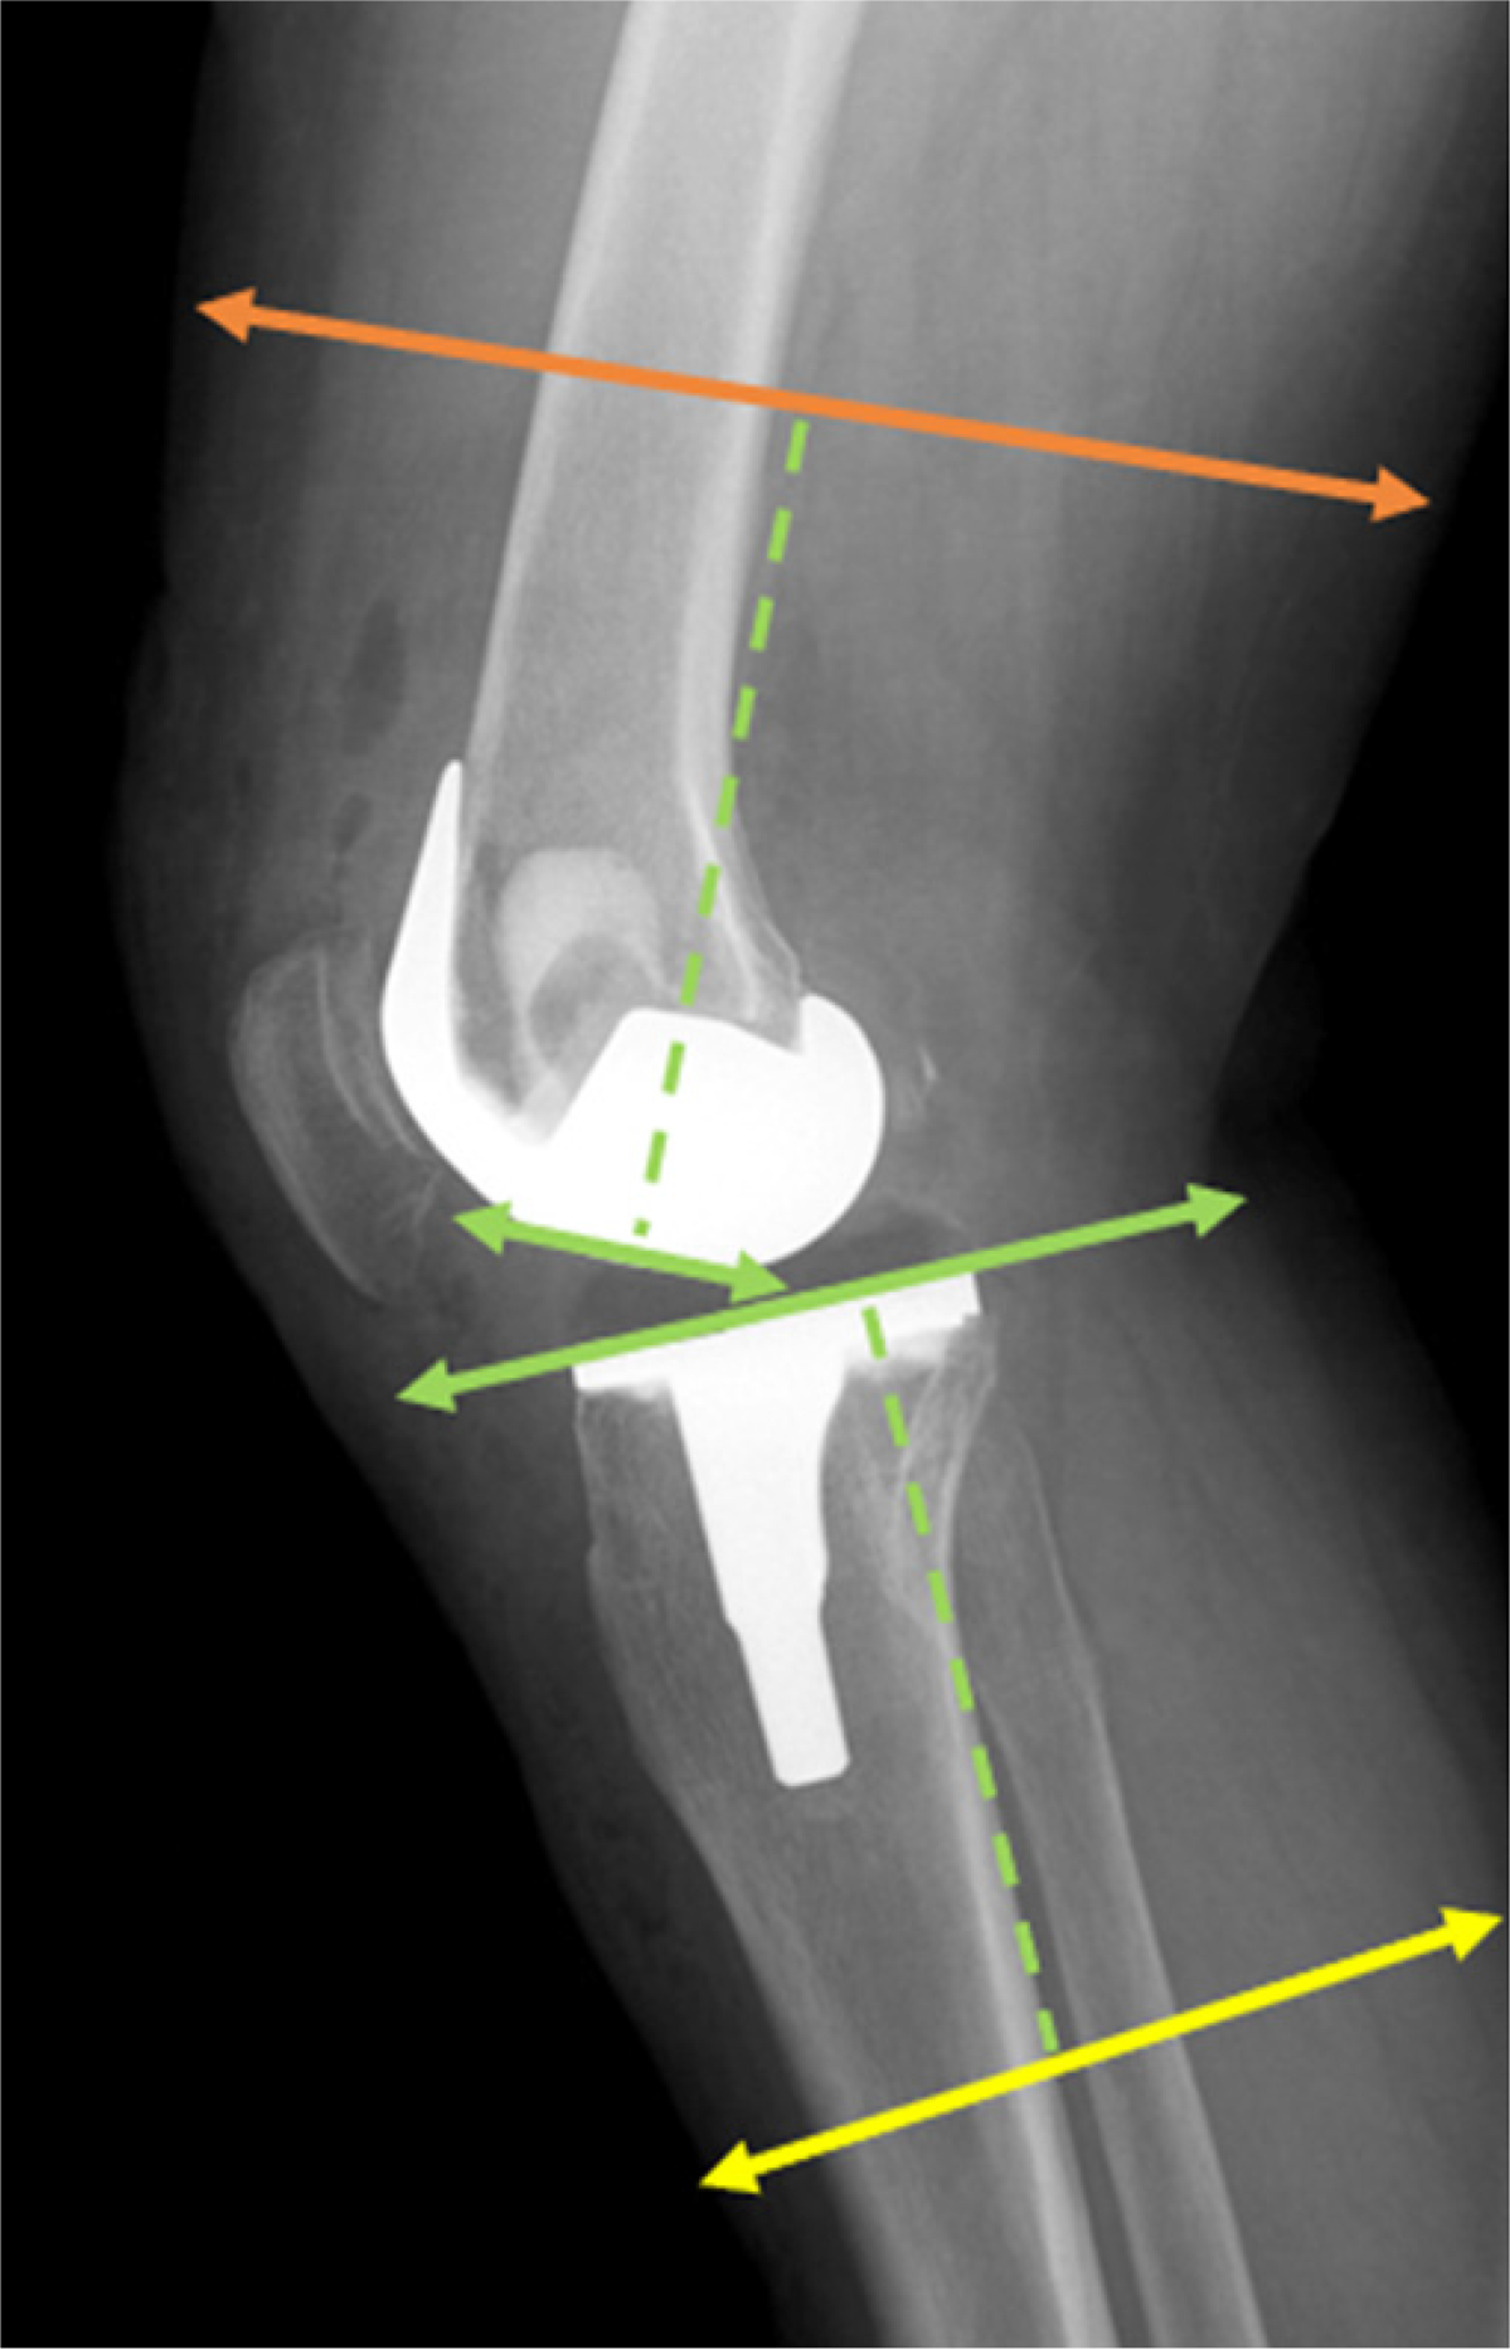

All surgical procedures were performed by the same experienced surgeon using a standard midline incision and medial parapatellar arthrotomy. In every case, a tourniquet was used for implant cementation, for an average of 18 minutes, and postoperative drainage was maintained for at least 12 hours. The postoperative protocol included chemical and mechanical thromboprophylaxis, unless specifically contraindicated. All patients were subjected to a weight-bearing and long-leg view X-ray examination in the standing position with antero-posterior and lateral projection performed prior to and following the surgery. All measurements were obtained from postoperative radiographs. The bone and limb widths were measured 10 cm above the intercondylar line and 10 cm below the tibial plateau parallel to the prosthesis weight-bearing surface (Figs. 1, 2). For further calculations, we took the mean value of our measurements from the lateral and antero-posterior side. Our measurements were conducted by 2 independent researchers, and the mean values of their results were recorded. The data obtained were then compared to a particular component size. Analysis of the radiographic images was performed using the INFINITT PACS system (INFINITT Healthcare, Seoul, South Korea). Besides radiographic analysis, we also performed clinical evaluation of our patients at admission and at the follow-up appointment approximately 1 year after the surgery. They were asked to fill out the KOOS and WOMAC questionnaires. All patients completed the questionnaires independently. The surveys were collected and assessed thereafter. Body mass index was calculated using the standard formula. To avoid potential bias, all data concerning participants were kept blinded. Informed consent was obtained from all subjects involved in the study.

Fig. 2

Lateral view of lower limb measurement areas. The green dashed line marks a distance of 10 cm from the intercondylar line and the tibial plateau, marking the femoral and lower leg measurement regions indicated by the orange and yellow lines, respectively.